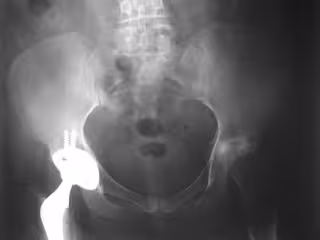

El estudio incluyó a más de 600 pacientes mayores de 50 años los cuales se sometieron a una cirugía por un tipo común de fractura de cadera: fractura del cuello femoral. Todos ellos vivían o caminaban independientemente antes de fracturarse la cadera. Los objetivos del estudio fueron cuantificar de manera descriptiva los cambios de los pacientes en el estado de vida y el uso de ayudas para caminar durante el año posterior a la fractura de cadera.